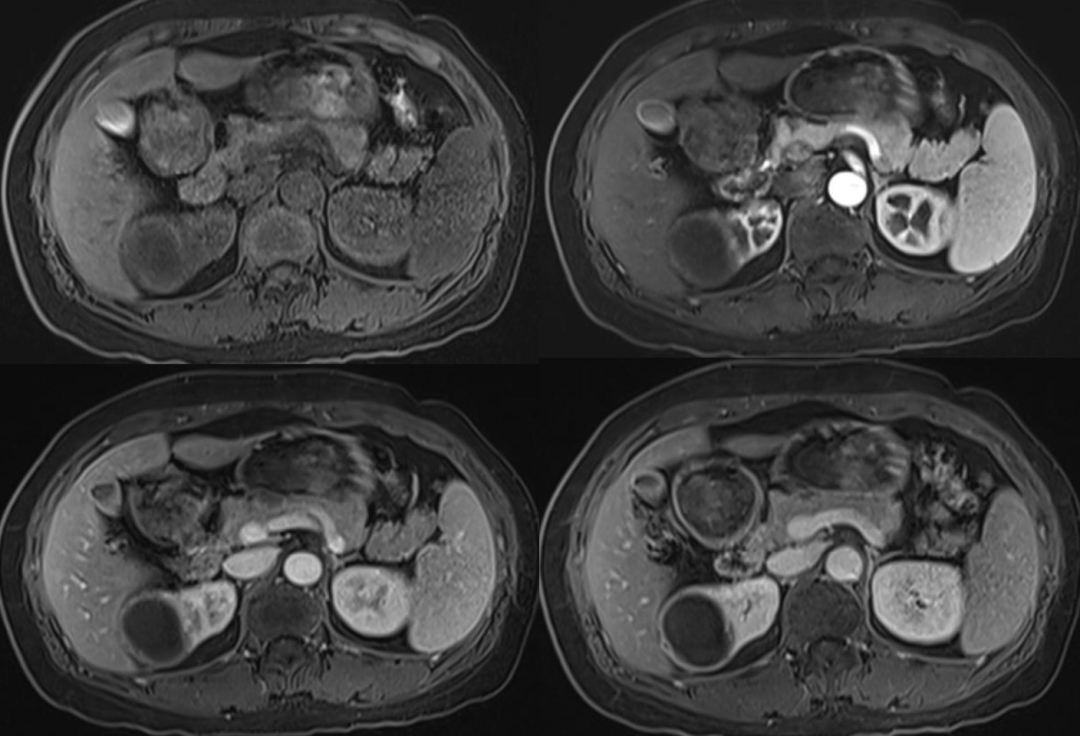

黄色肉芽肿性肾盂肾炎是一种慢性肉芽肿过程,被认为是亚急性/慢性感染导致慢性但不完全免疫反应的结果。最常见的是大肠埃希菌和奇异变形杆菌感染。其特征是肾实质损害、肉芽肿性脓肿及肾间质大量含脂肪的巨噬细胞聚积。含脂肪的巨噬细胞堆积。肾脏最终被大量反应性组织取代,伴有不同程度的肾积水,其环绕鹿角形

"熊掌征"表现为以肾盂肾盏为中心肾实质内多发囊性占位,其中部分囊为结石梗阻所致的肾积水,部分为黄色肉芽肿的脓腔;通常肾盏扩张为主,肾盂扩张常常不显,增强后,病变实性部分均匀强化,坏死区无强化,低密度区边缘环形强化。患肾体积增大或局限性隆起。常常伴有集合系统结石;肾皮质变薄;肾窦脂肪组织减少,多为慢性炎性反应性纤维组织增生所替代;肾周筋膜增厚、肾周间隙渗出积液,严重时可形成脓肿累及腰大肌。腹部X线平片典型的表现是受累的肾脏增大并有鹿角状结石,同侧腰大肌边缘模糊。超声显示肾脏轮廓变形,正常结构消失,中央可探及结石声影。